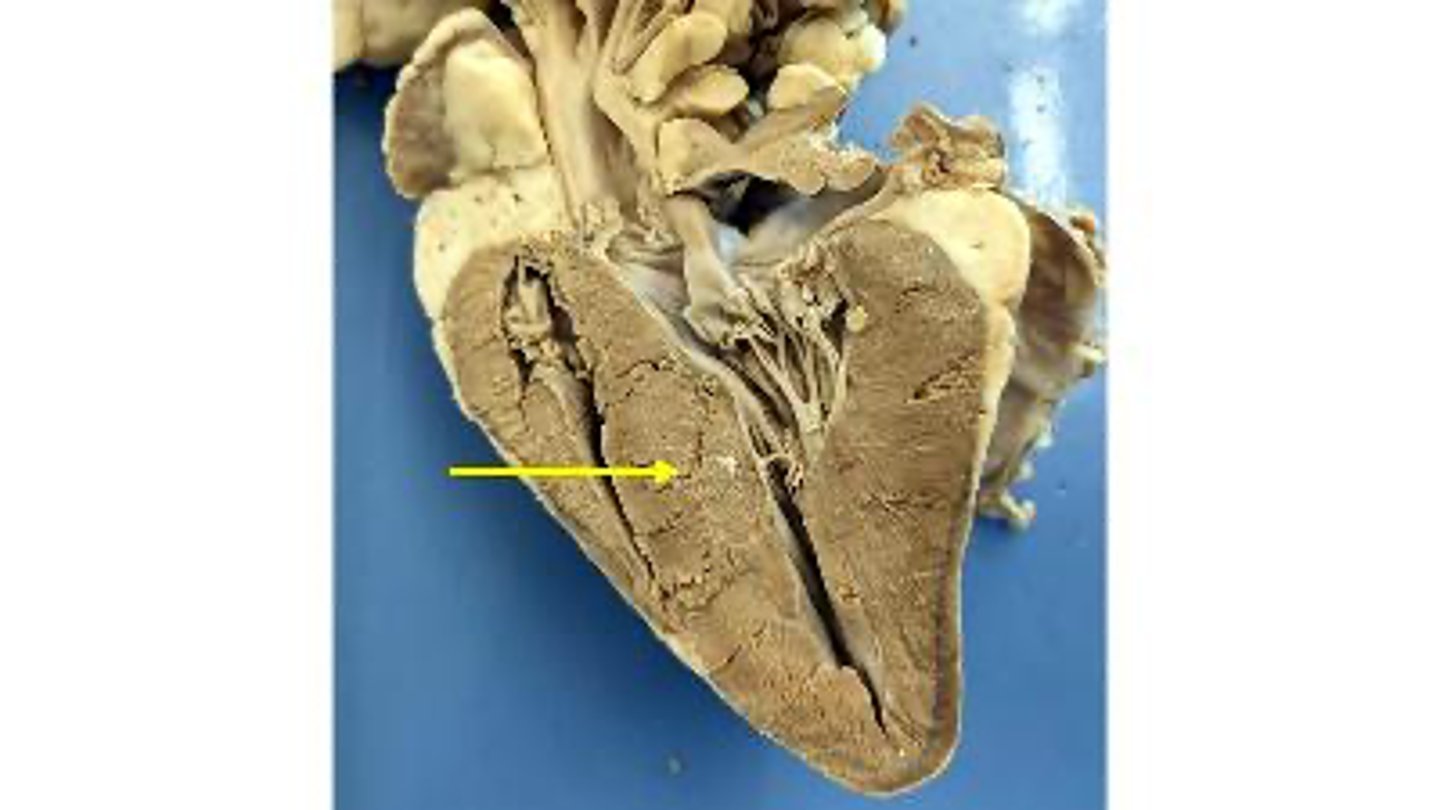

aortic valve

Name the membranous structure

right auricle

Name the ear-like structure

apex

Name the region of the organ

left ventricle

Name the chamber

interventricular septum

Name the dividing wall indicated

chordae tendineae

Name the structures

right ventricle